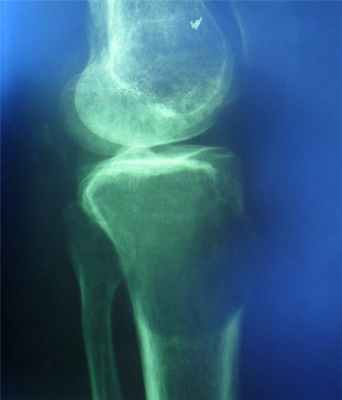

Гигантоклеточная опухоль

(остеобластокластома)

- состоит из клеток 2 типов- многоядерных гигантских и мелких одноядерных,

- поражаются люди в возрасте от 20 до 40 лет,

- локализация бедренная кость - дистальный конец, проксимальный конец б/берцовой кости, дистальный конец лучевой кости. Из плоских костей – тазовые кости и лопатка, очень редкая локализация в позвонках,

- одиночность и изолированность поражения,

- характерно расположение опухоли в эпиметафизраном отделе, который значительно вздут и деформирован, имеет вид крупнобугристого полушария, булавы,

- опухоль доходит до суставного хряща и обрывается,

- растет во всех направлениях, но главный рост происходит вдоль длинной оси кости в сторону с/3 диафиза кости,

- поперечник опухоли может увеличивать нормальный диаметр опухоли в 3-5 раз.

- ячеистый тип - опухоль состоит из отдельных камер, отделенных друг от друга полными и неполными перегородками (мыльные пузыри или неправильные соты),

- корковое вещество раздвигается, вздувается изнутри, истончается, надкостничных наслоений нет,

- при больших опухолях корковое вещество рассасывается и опухоль окружена со всех сторон тонкой скорлупой состоящая из стенок поверхностно расположенных ячеек.

- остеолитический тип – полное отсутствие ячеистого или трабекулярного рисунка, дефект кости вполне гомогенен,

- краевой блюдцеобразный дефект,

- корковый слой на пораженном месте рассасывается, а на границе с дефектом корка заострена, не подрыта и не имеет никаких периостальных наслоений,

- контуры дефекта резкие,

- патологические переломы в 12% случаев.